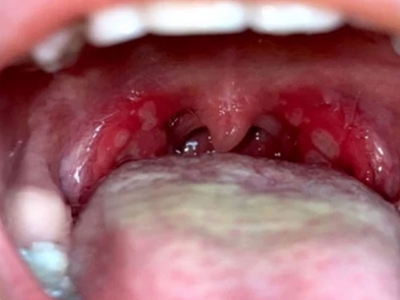

疱疹性咽峡炎典型体征为咽部充血,口腔黏膜出现数个灰白色丘疱疹或小水疱,直径1-2mm,周围绕以红晕,2-3日后,红晕加剧并扩大,疱疹破溃形成溃疡,表面覆有假膜白色或淡黄色,一般一周左右愈合。